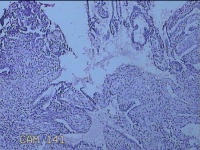

宫腔内容物

性别

女

年龄

47岁

临床诊断

1.异常子宫出血 2.慢性宫颈炎

一般病史

不规则阴道流血21天。

标本名称

大体所见

灰白暗红色不规则碎组织2.5x1.8x0.3cm一堆。

图2